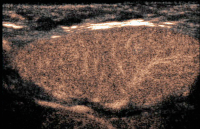

Abbildung 2: Pathologische Gefäßarchitektur. In diesem Fall sind mehrere Ausgangspunkte für Gefäßbäume zu erkennen. Starke Flowsignale sind auch in der Peripherie des Cortex zu erkennen. Lymphom (DLBCL)